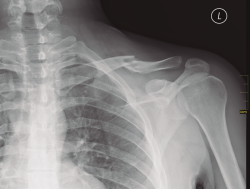

Existen distintos tipos de fracturas escapulares. En ocasiones, tras una fractura glenoidea (35%) (Figura 3), pueden producirse fracturas de coracoides (7%) (Figura 4) y también pueden ocurrir fracturas escapulares indirectas por caídas con la mano extendida(1,3,5).

Figura 4. Radiografía simple de fractura de coracoides.